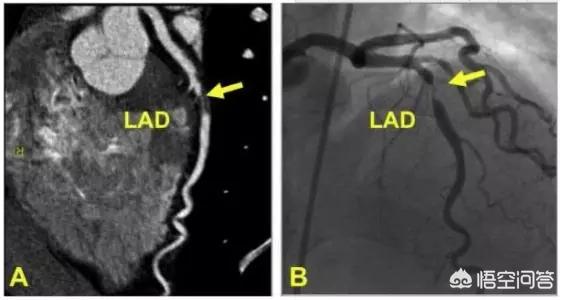

プロジェクトを見直す冠動脈造影またはCTA

ステント留置術は9~12ヵ月後に血管の状態を確認する必要があり、その時点での症状や血管の病態に応じて、医師が適切な検査を勧めます。

一般に、直接冠動脈造影は、まだ症状のあるエピソードがあり、血液透析が完全でなく、複雑な手技が必要で、糖尿病を合併し、多枝血管症がある患者に推奨される。

検討の結果、冠動脈の元の病変が悪化していないか、新しい病変が出現していなければ、抗血小板薬を徐々に中止することが可能である。